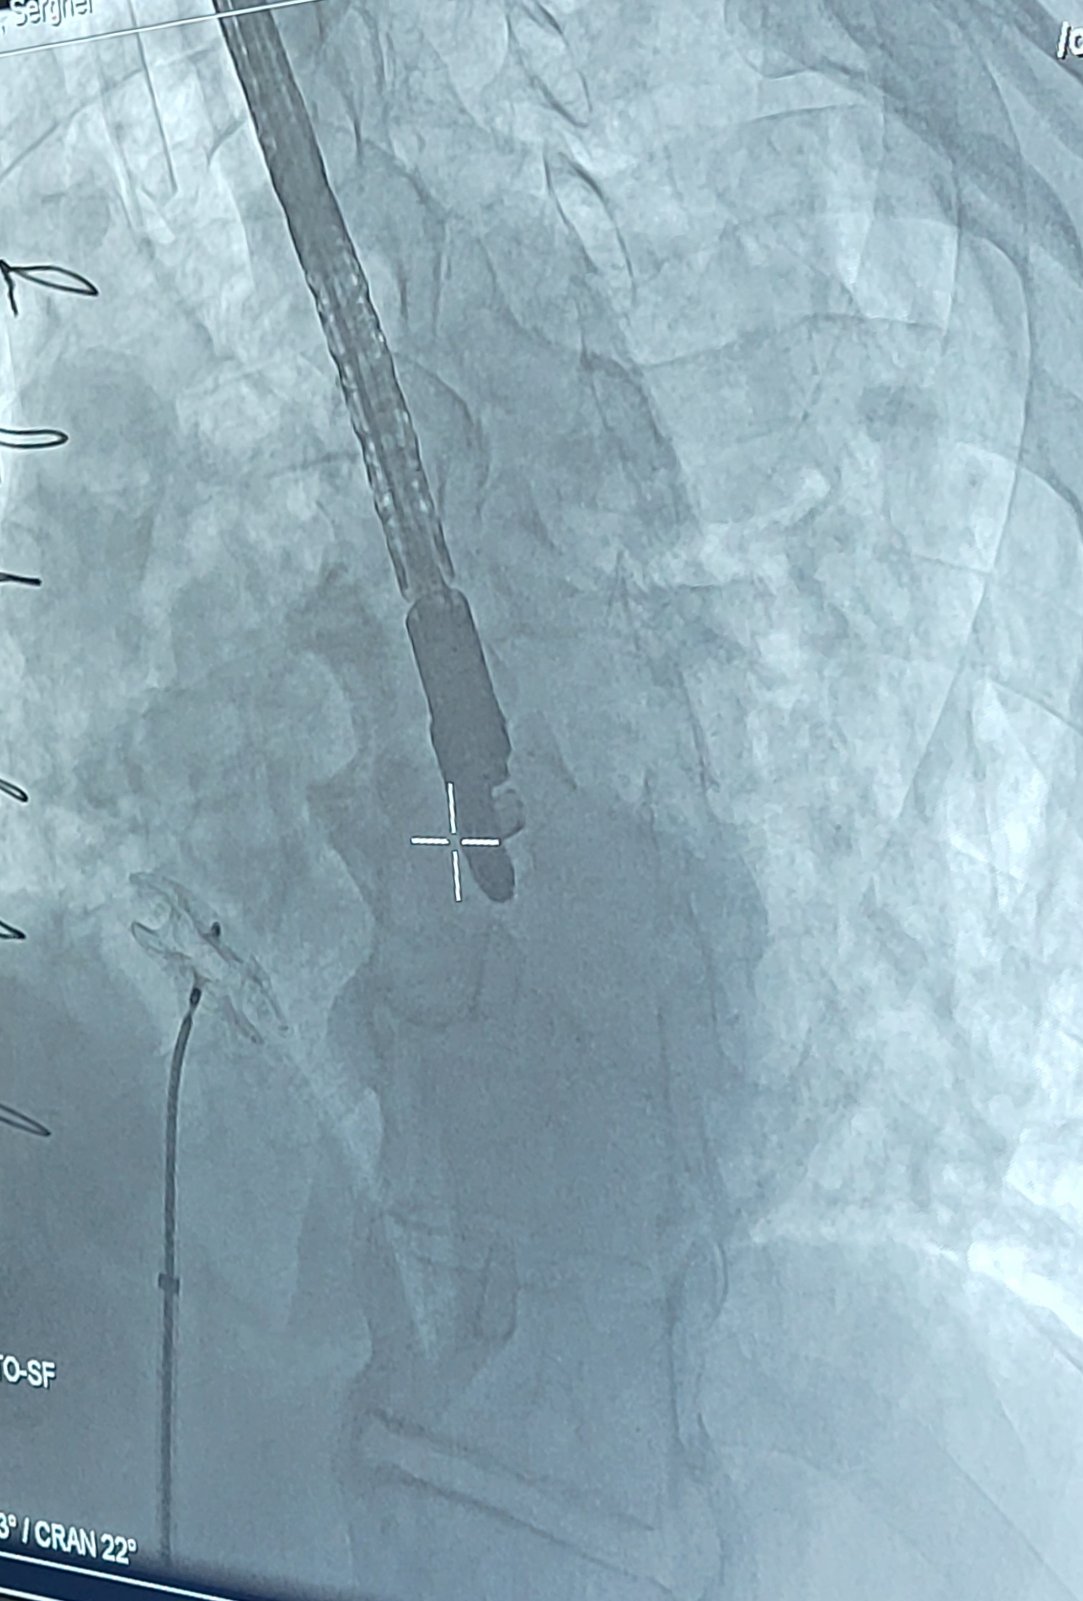

Ocluderul este un dispozitiv asemănător unei umbreluțe. Inițial acesta este pliat, iar după poziționarea lui exactă la locul defectului, umbreluța care prezintă două componente asemănătoare unor discuri atașate în porțiunea centrală se va deschide și va obtura defectul. Procedura este minim-invazivă. Se efectuează sub anestezie generală și poate dura între 60 și 120 de minute.